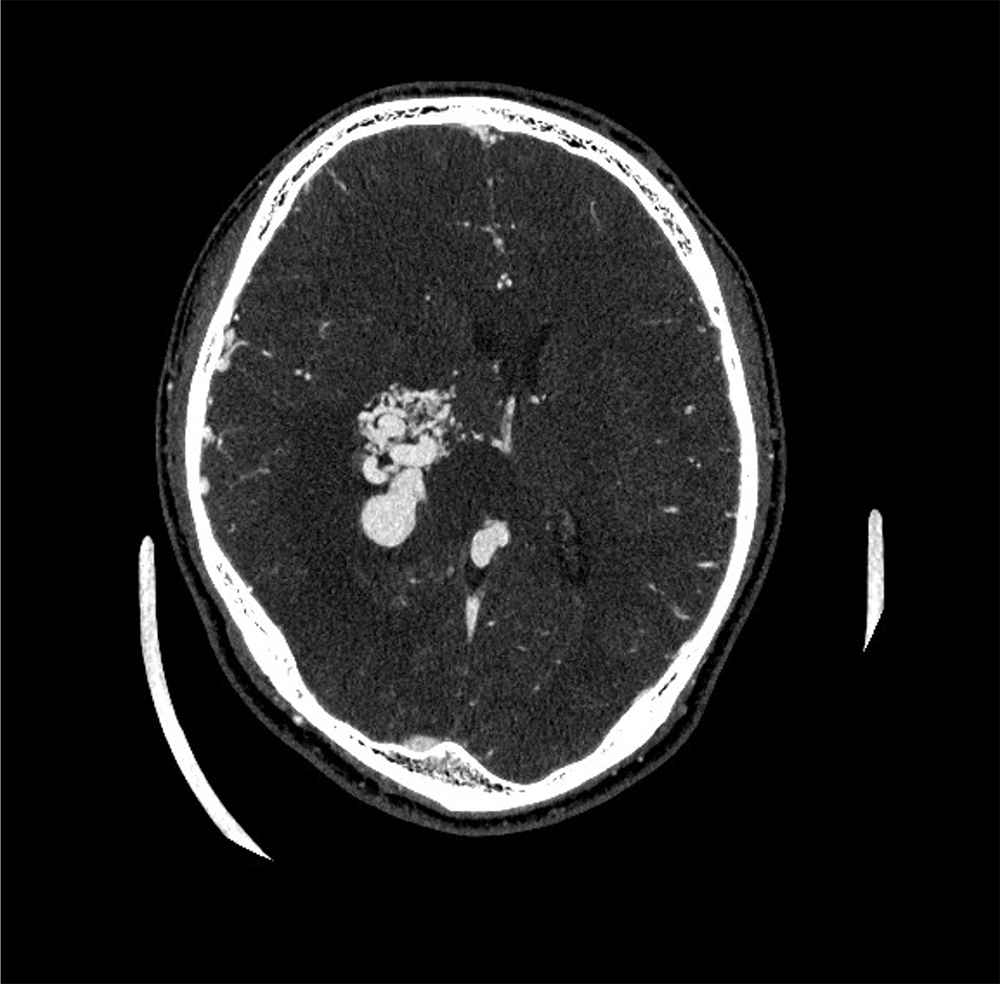

図1.Axial画像

AVMに高い造影効果が得られてる。

右頭頂葉から側頭葉に既知の出血を伴う脳動静脈奇形(AVM)を疑う病変を認める。AVM周囲に消退傾向の血腫と思われる高吸収域が認められ、周囲に浮腫性変化が拡大している。CT-AngiographyのVolume rendering画像では右内頚動脈~中大脳動脈を流入動脈として蛇行したナイダスが認められ、高度に拡張した導出静脈を介して下矢状静脈洞に還流していることが分かる。